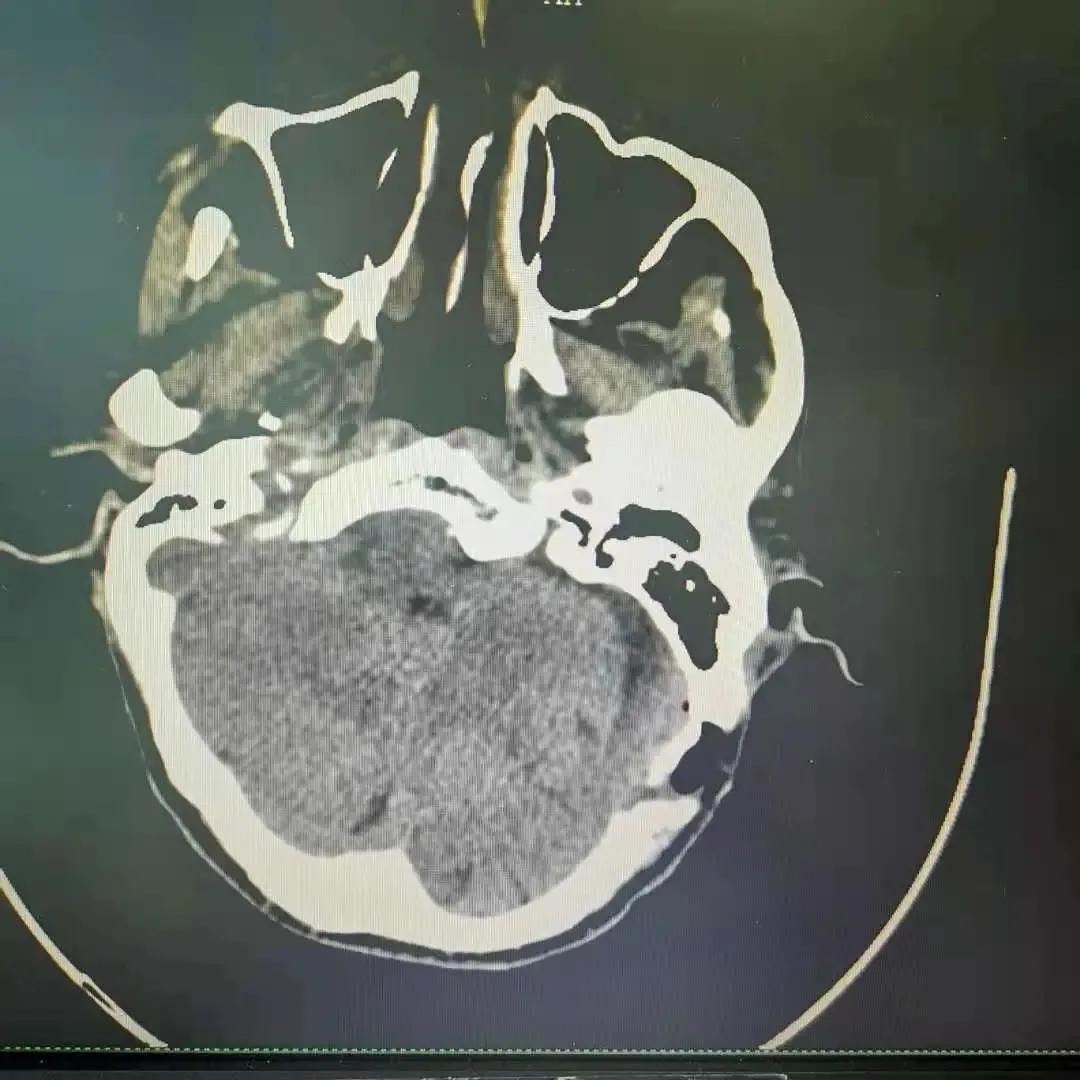

术后复查的头颅CT

手术结束后的第二天,柳先生感觉到左侧面部疼痛立即有了缓解,平时难捱的刷牙、洗脸、吃饭也不再是噩梦。经过一周治疗后,柳先生完全康复了,他谢过神经外科医师团队后,兴高采烈地出院了。